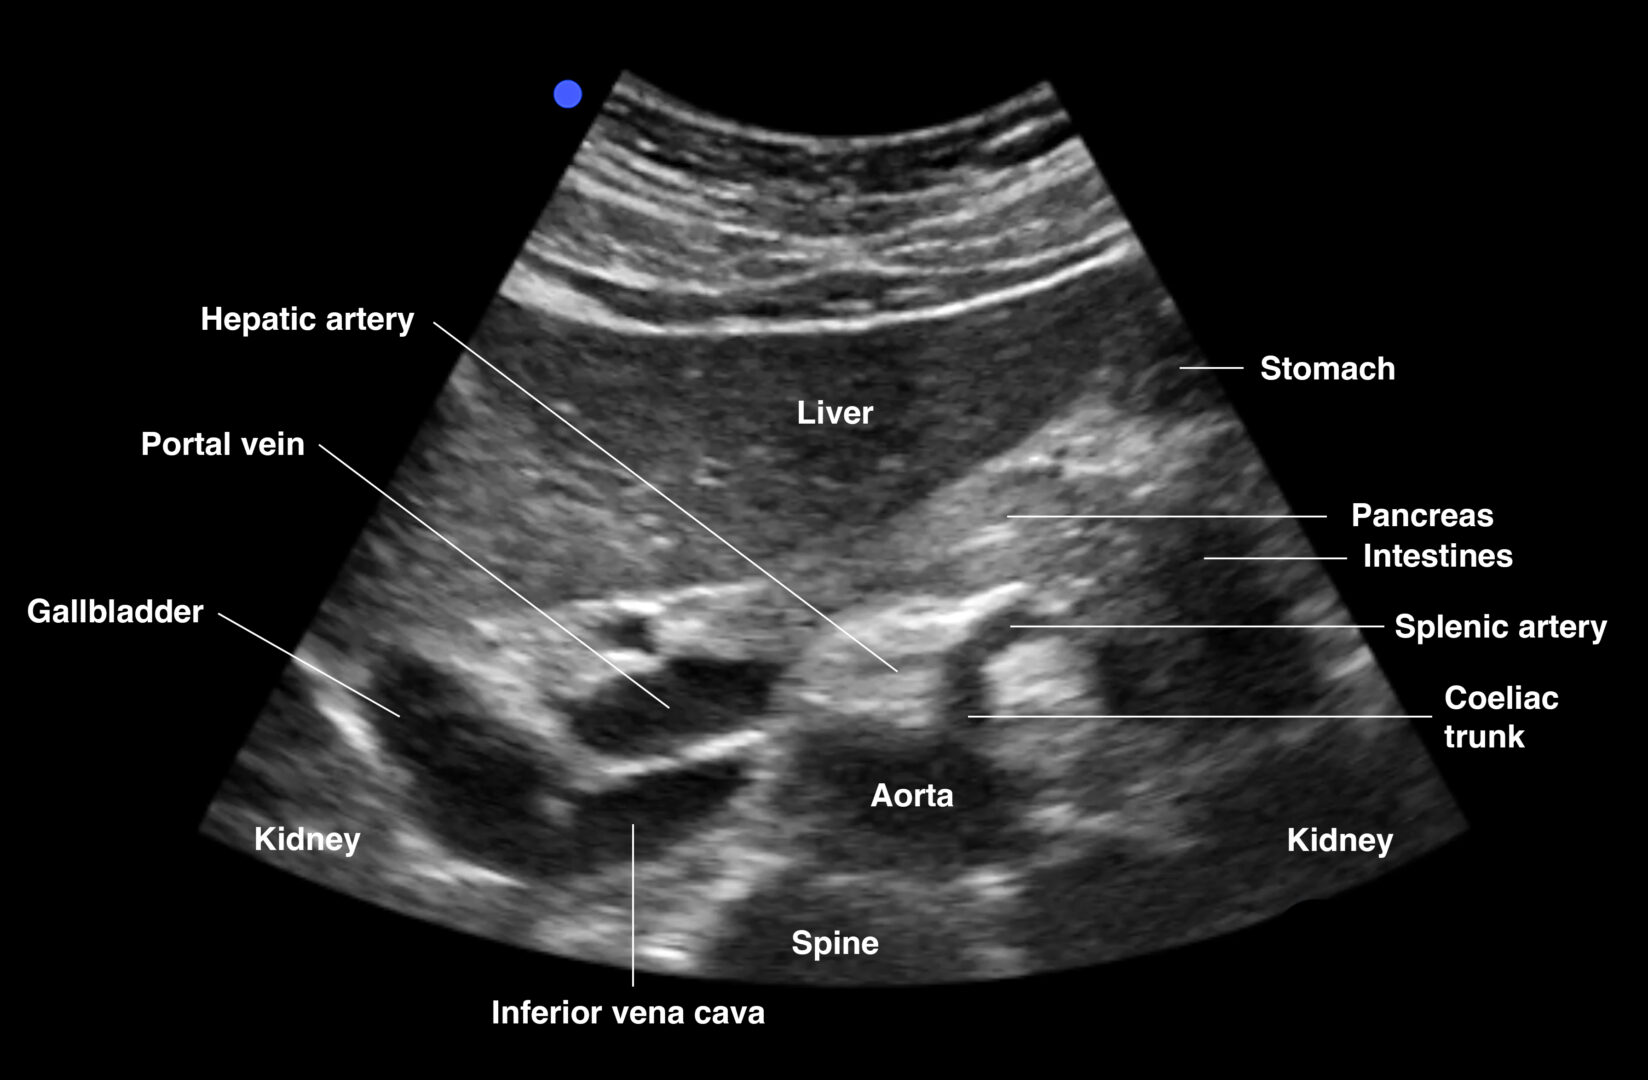

Proximal aorta

Transverse view of proximal aorta: aorta, IVC, celiac artery: splenic and hepatic artery (seagull sign), spine, liver, gallbladder

Transverse view of the proximal abdominal aorta.

Notes

- The left gastric artery is usually not visualized